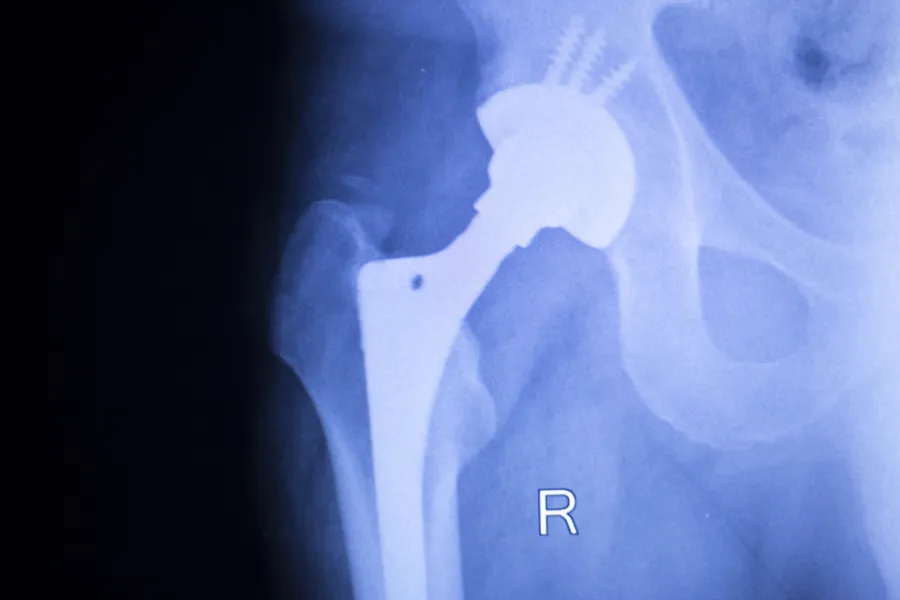

Eldre pasienter ble spart for påkjenningen av å måtte opereres på nytt da flere kirurger over hele landet gikk over til sementerte lårbenstammer i hofteproteseoperasjoner.

Foto: Colourbox

Særlig kvinner over 75 år og pasienter med hoftebrudd har nytte av at kirurgene går bort fra å bruke usementerte lårbenstammer til heller å benytte sementerte lårbenstammer i hofteproteseoperasjoner.

— Prosjektet ble satt i gang fordi vi observerte en økende bruk av usementerte lårbenstammer i Norge. Dette til tross for at alle nyere studier viser at risikoen for reoperasjoner er høyere dersom disse stammene brukes, enn dersom en bruker sementerte stammer. Risikoen er spesielt høy for å pådra seg brudd rundt proteser, hvilket medfører store reoperasjoner. Særlig høy er risikoen for de eldste pasientene, og spesielt for kvinner over 75 år og for pasienter med hoftebrudd, sier Jan-Erik Gjertsen.